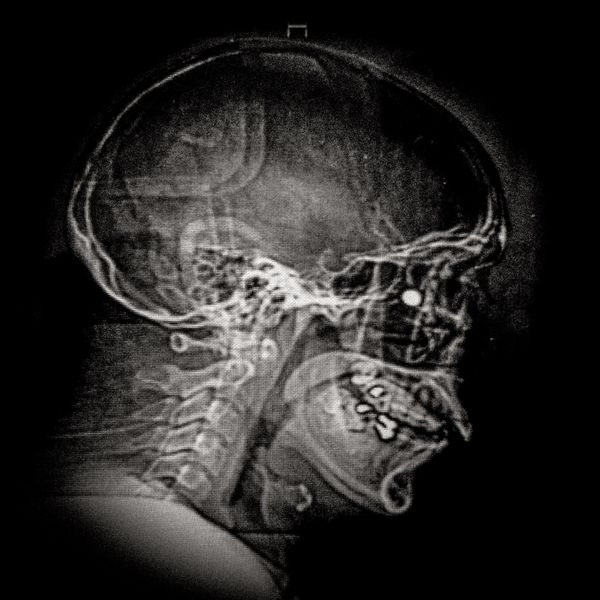

X ray showing the embedded pellet of Camilo Galvez (24) injured by chilean police during Santiago protests.

© Cristóbal Olivares - X ray showing the embedded pellet of Camilo Galvez (24) injured by chilean police during Santiago protests.

Camilo Galvez (24) Sound technician Lives in Puente Alto,Santiago Camilo was hit by a pellet that lodged into his right eye on November 15th, 2019, near the Universidad Católica de Chile in Santiago. His diagnosis was an eye burst with total loss of the right eye and fracture. “I lost an eye not because I had an accident, but because somebody shot me on purpose to mutilate me, and that is pretty hard. To think and reflect about this is very abysmal, it generates a lot of fear. When they shoot our eyes one becomes marked, it is their way of marking us, and leaves us with a psychological trauma beyond the physical mutilation.”